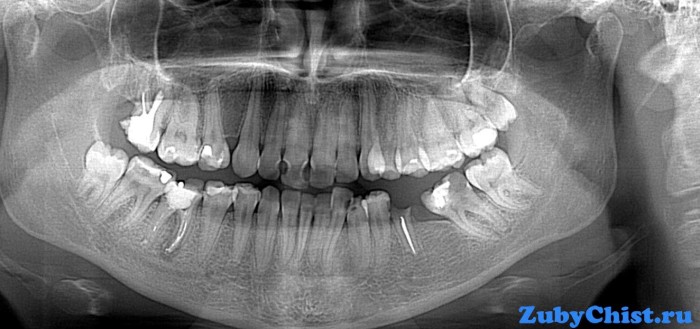

Установка протеза представляет собой трудоемкий процесс. Перед процедурой проводятся подготовительные мероприятия, включающие тщательную диагностику.

Перед процедурой выполняется лечение, обточка и специальное депульпирование. Если сточились передние зубы, то выполняется пломбировка корневых каналов, удаление камней и лечение.

Это защитит от повреждения пульпы при выполнении обточки. У жевательных резцов нервы часто оставляют.При подготовке резца с одним корнем делается устранение нерва.

Депульпирование осуществляется следующим образом:

1. Удаляется нерв.

2. Увеличиваются корневые каналы.

3. Выполняется пломбирование каналов.

4. Осуществляется пломбирование остальной части.